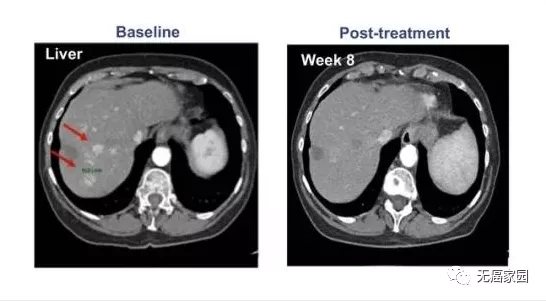

其中1例晚期肝癌患者接受了瘤内注射CAR-T治疗,治疗后肝脏病灶代谢基本消失。

CAR-T细胞注射60天后,虽然2个肺部结节的尺寸没有显著的改变,但在第10天时肝脏肿瘤病变(1.2×1.3cm)显著收缩,注射GPC3-7×19 CAR-T细胞第32天后则完全消失。

患者没有任何毒性作用,并且根据 CT 上的标准实体瘤反应评估标准 (RECIST) 1.1 版进行了分期评估,显示部分缓解 (PR)。